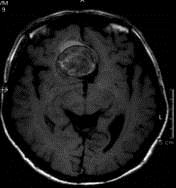

病历摘要:??患者男性,56岁,因右侧视力下降伴视野缺损2个月来院就诊,诉头痛,无明显头晕,无视物重影,无恶心呕吐,无肢体抽搐,无肢体乏力,胃纳佳,大小便...

问题 病历摘要:??患者男性,56岁,因右侧视力下降伴视野缺损2个月来院就诊,诉头痛,无明显头晕,无视物重影,无恶心呕吐,无肢体抽搐,无肢体乏力,胃纳佳,大小便正常,既往史无特殊,入院检查:神志清楚,言语清楚,体毛分布正常,左侧视力4.6,右侧视力4.0,粗侧右颞侧视野缺损,左侧正常,颈软,四肢肌张力正常,肌力正常,病理征(-)。 对于动脉瘤,下列那些是翼点入路的适应症?提示:该患者采用左侧翼点开颅夹闭动脉瘤

选项 A.颈内动脉-眼动脉动脉瘤 B.大脑前动脉动脉瘤 C.前交通动脉动脉瘤 D.颈内动脉末端动脉瘤 E.大脑中动脉动脉瘤 F.后交通动脉-颈内动脉动脉瘤 G.基底动脉末端动脉瘤

答案 ABCDEFG

解析 ABCDEFG